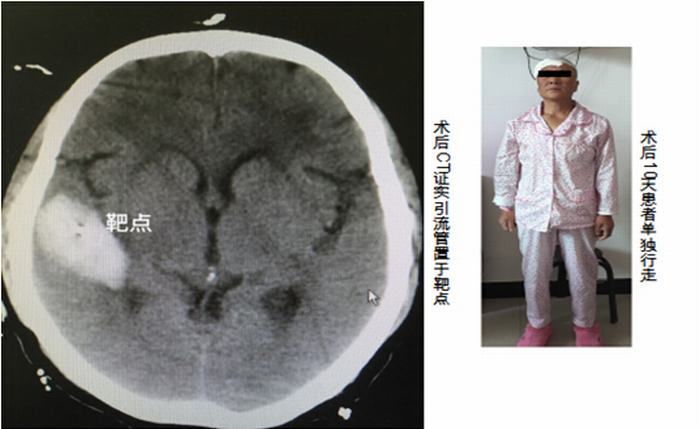

术前安装定位头架后进行CT扫描

2016年4月21日凌晨2点,闫女士突然出现头痛、左侧肢体无力等症状,当晚即被家人紧急送医,经查,她大脑的右侧颞叶出现脑出血。经过细致的准备,我院神经外科医护人员为闫女士实施了脑立体定向手术,术前安装头架,头颅CT扫描,设定靶点并计算坐标,术中安装弓形架等,将引流管精确植入靶点---血肿正中心,顺利抽出血肿,术后CT验证立体定向手术精确。现经治疗10多天后患者已独立下床活动,恢复理想。